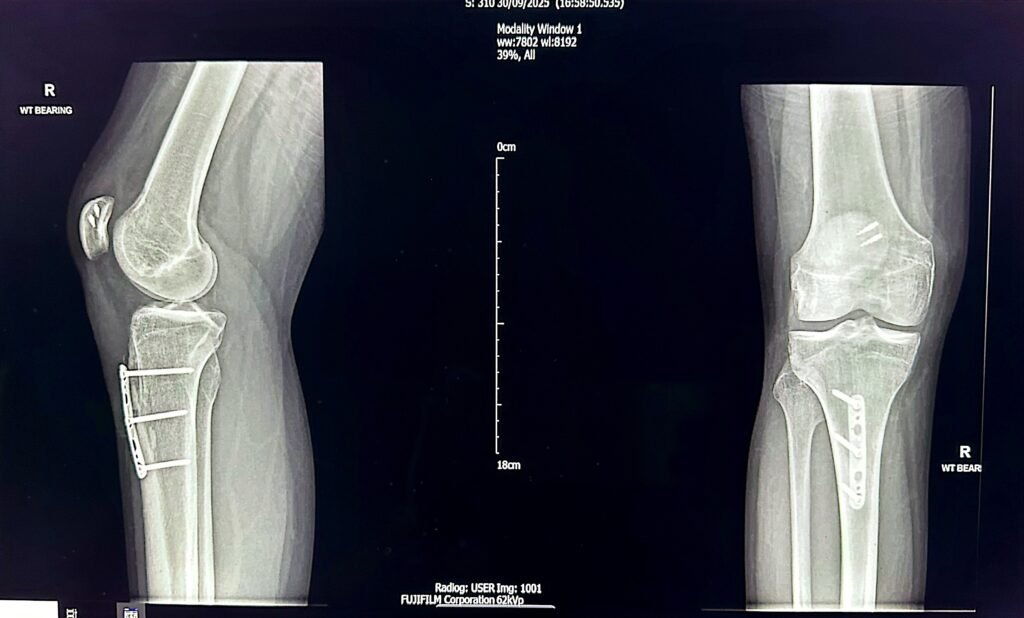

MPFL reconstruction is often combined with tibial tubercle osteotomy depending on the presenting pathology. This procedure involves the surgical movement of the tibial tuberosity (the area on the shin bone where the patellar tendon attaches) either medially (inwards) or inferiorly or both depending on the risk factors present. The fixation is held with a plate /3-4 screws to hold the repositioned new bone in its new position. It takes 3-4 months for the bones to heal completely.

Below is the X-ray of a young person who has undergone MPFL+TTO surgery 6 months ago, the osteotomy site in tibia has completely healed.